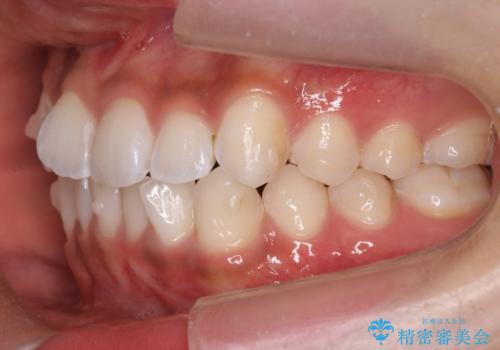

前歯のがたつき 1年かからず治療 マウスピース矯正

- 前歯のがたつきを主訴に来院。

インビザラインで歯を抜かずに並べました。

マウスピースの延長(リファインメント)もなく、短期間で綺麗に並びました。